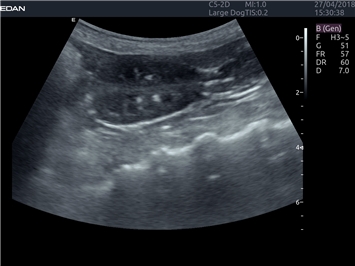

EDAN Acclarix LX4 VET представляет собой профессиональную ультразвуковую систему, специально разработанную для ветеринарных исследований. Сочетание стабильности, высокой производительности и эффективности делает эту систему идеальным выбором для современной ветеринарной практики.

• Универсальные датчики для различных видов животных

• Специализированные предустановки для ветеринарных исследований

• Гибкие протоколы исследований